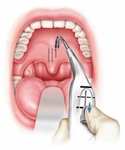

Damak Yarası Tedavi YöntemleriDamak yarasının tedavisi genellikle multidisipliner bir yaklaşım gerektirir. Aşağıda tedavi yöntemleri sıralanmıştır:

Hamilelikte Tedavi Sürecinde Dikkat Edilmesi GerekenlerHamilelik süresince, damak yarası riski taşıyan kadınların aşağıdaki hususlara dikkat etmeleri önemlidir: